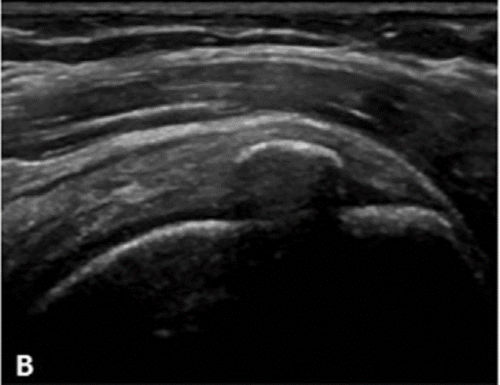

Υπερηχογραφική απεικόνιση της ασβεστοποίησης του ώμου (Farin)

Στην κλινική πράξη είναι αυτή που δίνει τις πιο αξιόπιστες πληροφορίες για τη σύσταση της ασβέστωσης.

| Τύπου Α: Υπερηχογενής με έντονη ακουστική σκιά | Τύπου Β: Υπερηχογενής με ήπια ακουστική σκιά | Τύπου C: Υπερηχογενής χωρίς ακουστική σκιά |

Με βάση αυτή την ταξινόμηση μπορούμε να εκτιμήσουμε την αποτελεσματικότητα μιας θεραπείας Barbotage

Με λίγα λόγια, όταν η ασβέστωση είναι μαλακής ή μέτριας σκληρότητας, το αποτέλεσμα της θεραπείας Barbotage προβλέπεται άριστο/πολύ καλό ενώ αν είναι σκληρής σύστασης τότε το αποτέλεσμα θα είναι μέτριο/φτωχό

(καλύτερη ένδειξη για barbotage: ασβέστωση Farin B και C , Gartner/Hayer II,III)